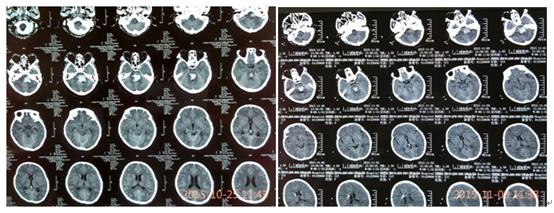

治疗前后,患者脑部影像图像对比

入住重症监护病房后,创伤脑血管神经外科主任金永健博士高度重视,迅速组织脑血管病医疗团队为患者进行了留置口咽通气道改善通气,降压、止血、健脑等治疗,并请麻醉科紧急会诊行气管插管、呼吸机辅助呼吸,经上述急救,患者病情略稳定。但2天后,患者意识障碍加重呈深昏迷状态,频繁恶心、呕吐,双侧瞳孔中央位、散大固定,复查头颅CT提示:脑干出血进一步增多、量约14ml,全脑干出血破坏脑干上行激活系统,并破入四脑室,梗阻性脑积水!患者病情再次告病危!金主任立即决定在床旁局麻下行“双侧脑室外引流术+换能器植入术”,缓解颅内高压并持续监测患者颅内压力变化。术后,患者意识障碍无明显缓解,舌后坠明显、呼吸困难伴痰液增多,中枢性高热40℃以上伴应激性溃疡;针对颅内高压,主管医生立即予以尿激酶溶通四脑室积血,恢复脑脊液循环;床旁行“气管切开术”管理呼吸道,予以冰毯机物理降温,亚低温治疗减轻脑水肿和降低脑耗氧量及颅内压,冰盐水及止血药物3小时一次胃管注入控制胃肠道出血;期间患者循环系统紊乱,心率较快、达130-170次/分,科室遂请心内科会诊协助控制心率;患者血管挛缩、输液困难,在B超导引下留置PICC成功,保证临床救治工作的有序进行。后科室再请呼吸内科会诊,协助控制肺部感染。在全科医护人员及多学科通力协作下,患者的病情终于得到了控制,成功度过了脑干出血最危险的第4天、第5天、第6天、第7天!

患者病情稳定一周后,复查头颅CT提示:脑积水明显缓解,但仍有交通性脑积水,难以耐受夹闭脑室引流管24小时,所以不能拔除引流管,否则仍会出现急性脑积水导致生命危险。而长期留置引流管又会加重患者脑室感染的风险,对于患者本人来说也是雪上加霜、难以承受的风险,可能会葬送之前的所有努力!阴云再次笼罩在医护人员及患者家属的心里,患者家属因难以支撑这种病情的反复变化及现实的压力,多次要求自动出院听天由命,但关键时刻的放弃或者是犹豫,结局就是死亡!救治团队重新审视病情,思索解决的方案,决心间断夹管并辅助腰椎穿刺的传统做法,终于,在2周的时限内成功拔管,患者的颅内压监测始终在10mmHg正常范围内,并且在2天的时间内成功复温,从亚低温恢复正常体温,没有高热、惊厥、休克及心率紊乱等复温过程中常见的合并症;再观察了3天,患者生命体征均较平稳,并且存在情感反应,在住院17天后顺利出院,回家继续康复(高压氧)治疗。